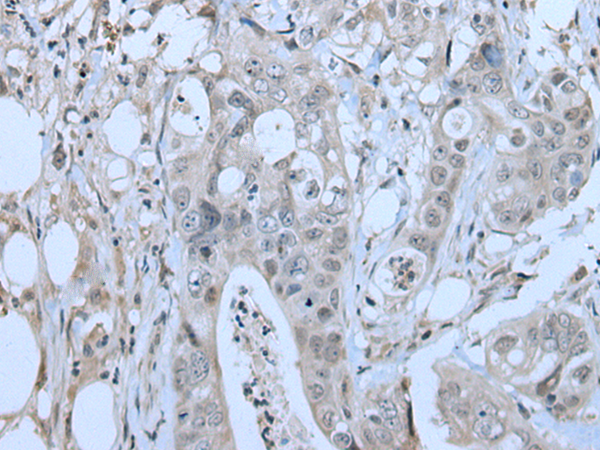

IHC positive control: |

Human lung carcinoma tissue |

IHC Recommend dilution: |

50-100 |